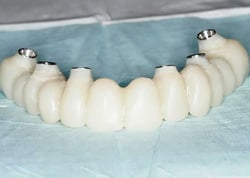

There is a philosophy of minimal bone reduction surging in full-arch dentistry. Most full-arch, immediate-load, cases completed today do not follow this philosophy. They involve leveling the bone to a flat surface and meeting that surface with a prosthetic, often with what is considered excessive alveoloplasty. There is an alternative and it is a part of the GuidedSMILE family of products – GuidedSMILE Natural.

GuidedSMILE Natural follows the same beginning as standard CHROME GuidedSMILE cases – Pin Guide, Fixation Base, and Osteotomy Guide. Then, a special scalloped guide aids with the visualization and contouring of the alveoli’s reduction to create socketing for the tissue and prosthetic. This is technique sensitive and we like to send one of our experienced technicians chairside for guidance for at least your first case.

The prosthetic is delivered during surgery and then converted in several months using a duplicate RAPID Appliance that was picked up during surgery.

A Patient Case Study

CHROME Natural Maxillary